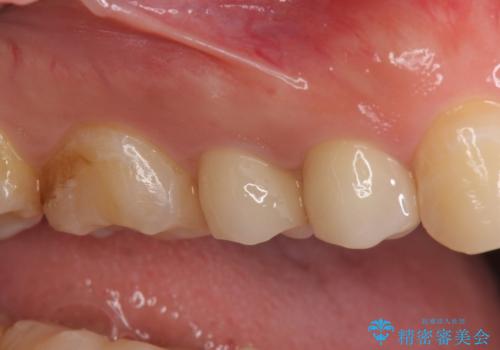

- 右上の銀歯を白くしたいといらっしゃった方の症例です。

右上4、5番目の歯はオールセラミッククラウンによる補綴、6番目の歯はセラミックインレーによる修復を行いました。

今回用いたオールセラミッククラウンは、ジルコニアフレームという白い素材の上にセラミックを盛っているため審美性が非常に高いのが特徴です。

またジルコニアは人工ダイヤモンドの材料にも使われているほど高い強度を持っており、そのためオールセラミッククラウンは審美性だけでなく、奥歯やブリッジの補綴も可能とするクラウンです。

当院のセラミックインレーはemaxという強度と審美性に優れた材料を使用しています。

またプレス方式でインレーを製作しているため、削り出しで製作するCADCAMより優れた適合性も持ち合わせており、虫歯が再発しにくい修復物です。